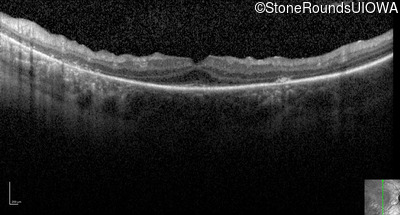

Optical Coherence Tomography - Right - 20/50

Exemplar / OCT Stack